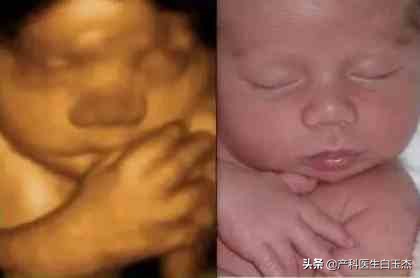

近几年很多准妈妈都会给宝宝做四维彩超,作为宝宝珍贵的“零岁写真”!但是你有没有过这样的经历,在宝宝出生后的某一瞬间,也许是姿势、也许是表情,会和四维照片非常相似?这不,下面这些宝宝就和自己的四维照片超级同步,表情姿势全都一样。

动作简直神同步~~~